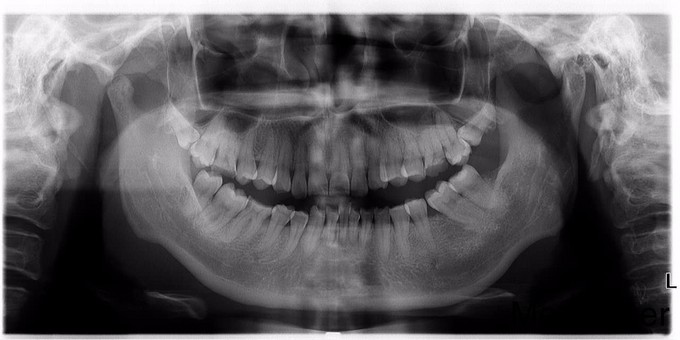

1113水平阻生智齿的拔除光14

两侧后牙区不适,求治

水平阻生智齿拔除